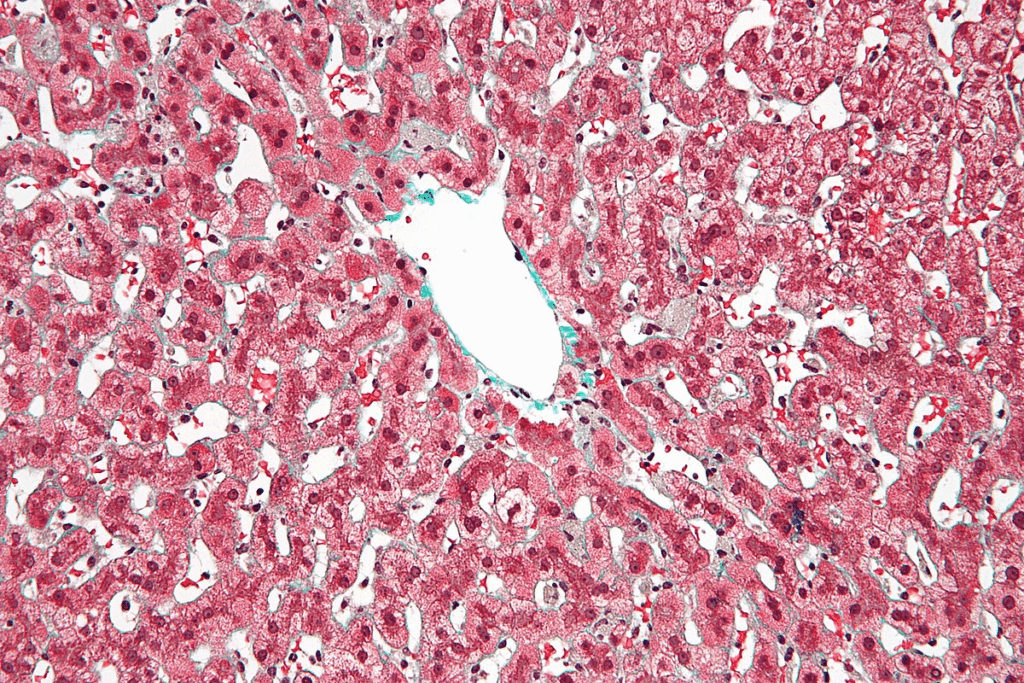

Pathological Examination of Hepatoblastoma Tissue

Histological Subtypes and Their Significance

Hepatoblastoma has different types based on how the tumor looks under a microscope. Each type has its own traits and how well it might do in treatment. The main types are:

- Epithelial type

- Mixed epithelial and mesenchymal type

- Small cell undifferentiated type

Knowing these types is important. It helps us choose the best treatment for each child. Some types might do better with certain medicines.

Immunohistochemistry and Molecular Testing

Immunohistochemistry and molecular testing are also important. They help us:

- Find special markers in the tumor

- Learn about the tumor’s genes

- Find the right therapy for the tumor

Immunohistochemistry helps us tell hepatoblastoma apart from other tumors by looking at proteins. Molecular testing shows us genetic changes that might be treated with specific medicines.

Interpretation of Biopsy Results

Understanding biopsy results needs a lot of knowledge and skill. We look at many things, like:

- The tumor’s type

- Special markers in the tumor

- Genetic changes found by molecular testing

Getting biopsy results right is very important. It helps us make a treatment plan that fits each child’s needs.